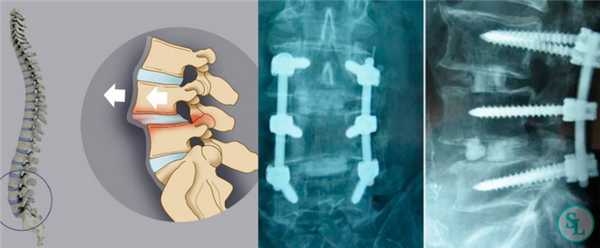

Транспедикулярная фиксация или ТПФ - операция, при которой позвонки фиксируются и стабилизируются при помощи специальных имплантов (транспедикулярных винтов). В каждом позвонке есть точка ввода винта, которую установил в 1985 году Рой Камилл — это точка пересечения поперечного отростка позвонка с верхнем суставным отростком. С помощью специальных инструментов в эту точку, вкручиваются винты определяя анатомически правильное расположение позвоночника, тем самым излечивая заболевание. Первые попытки установки имплантов были в 60-70 гг. прошлого века и с тех пор является «золотым стандартом» в лечения переломов и различных заболеваний позвоночника.

В «SL Клиника» выполняются все виды оперативного лечения, связыные с транспедикулярной фиксацией позвоночника по доступной стоимости с пребыванием в комфортабельном стационаре и с обеспечением тщательного врачебного контроля над протеканием восстановительного периода.